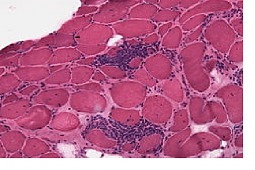

Badacze japońscy oceniali przydatność tomografii wysokiej rozdzielczości (HRCT) w ocenie rokowania u pacjentów z rozpoznaiem PM/DM. W grupie 51 chorych w jednoczynnikowej analizie wykazano, że DM z nieznacznymi lub bez klinicznych cech zajęcia mięśni (amyopathic DM, ADM), gorączka powyżej 38 st.C, stężenie ferrytyny przekraczające 500ng/ml, obecność przeciwciał anty-CADM-140 oraz występowanie zmian śródmiąższowych pod postacią zagęszczeń zlokalizowanych poniżej poziomu dolnych żył płucnych obwodowo lub okołooskrzelikowo lub o typie matowej szyby, wykazywały istotny związek z 90- dniową śmiertelnością. Analiza wieloczynnikowa wykazała, iż obecność opisanych wyżej zmian śródmiąższowych oraz przeciwciał anty-CADM-140 były niezależnymi czynnikami ryzyka 90-dniowej śmiertelności. Opisywane zminy śródmiąższowe mogą występować pod postacią m.in. zorganizowanego zapalenia płuc (organized pneumonia, OP) lub rozlanego uszkodzenia pęcherzyków płucnych (diffuse alveolar damage, DAD) i przebiegać z gwałtownie postępującą niewydolnością oddechową. Wydaję się, że przebieg PM/DM-ILD może być zróżnicowany w zależności od populacji (ADM źle rokuje w populacji japońskiej, w populacji zachodniej odznacza się natomiast dobrym rokowaniem; ponadto występowanie przeciwciał anty-CADM-140 częściej odnotowywane jest w krajach azjatyckich).